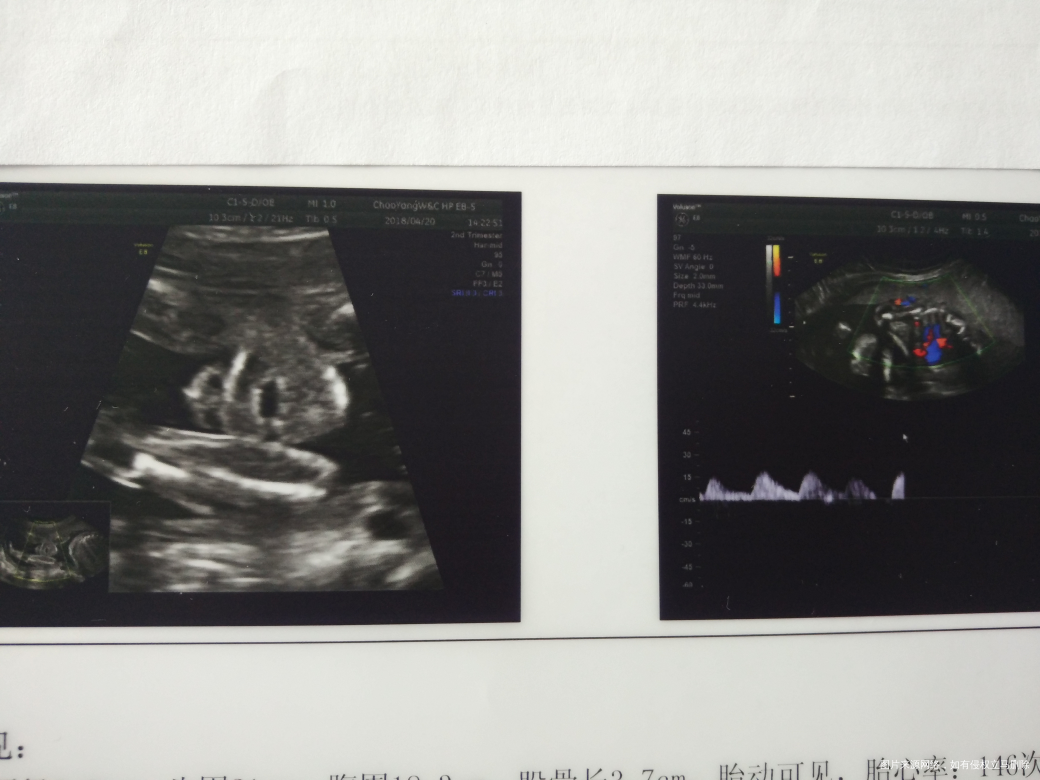

建议胎儿超声心动检查是心脏有什么问题吗?

您好,这个检查没有明显异常,只是常规建议。